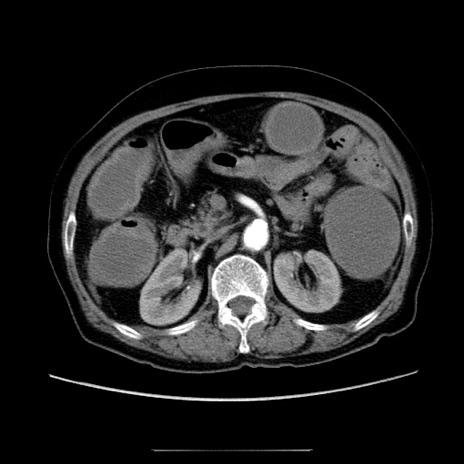

症例5(横断像)

【症例】70歳代女性

【主訴】お腹が張る

【現病歴】1週間くらい前から腹部膨満の自覚あり。昨日夜から増悪したため、本日救急外来受診。

【身体所見】意識清明、BT 36.5℃、BP 165/106mmHg、HR 80bpm、SpO2 98%、腹部:膨満、軟、自発痛・圧痛なし、触診にて不快感あり、腸蠕動音:減弱

【データ】WBC 12600、CRP 1.04